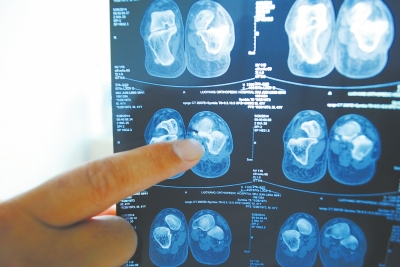

X光片顯示,確實有一根殘留的螺絲釘。

“我找到醫院,醫院說他們沒有責任。”太康縣毛莊鎮農民吳俊領近日向本報投訴,2012年10月,他因左腳跟粉碎性骨折,在太康縣民族骨科醫院做了鋼板固定手術,并于數月后做了鋼板取出手術。但一年之后,吳俊領仍感覺手術傷口處隱隱作痛,并伴有膿水流出,經檢查,竟還有一根螺絲釘殘留在里面。

今年4月,正在浙江的吳俊領忽然感覺手術傷口處隱隱作痛,并有膿水流出。他到醫院拍片檢查后,被告知左腳跟傷口內殘留有一根螺絲釘。

于是,吳俊領拿著X光片到太康縣民族骨科醫院討要說法。“你不是說傷口內的固定鋼板物被取凈了嗎?這X光片上咋還殘留一個螺絲釘啊?”一見到當時給自己做手術的醫生,吳俊領就問道。醫生當即準備帶領吳俊領到手術室打開傷口查看情況,但吳俊領已對這家醫院失去信任,最終到洛陽市一家他信任的醫院做了殘留螺絲釘取出手術,住院18天后康復出院。出院后,吳俊領要求太康縣民族骨科醫院院賠償其經濟損失,但遭到拒絕。